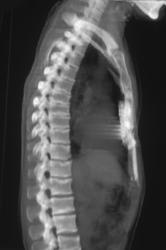

Incidental Soft Tissue Mass in Gluteal Muscle